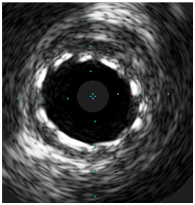

38 year old male patient with 15 packs per year smoking history presented to a peripheral hospital with acute onset typical chest pain for 30 minutes. His ECG revealed ST- Elevation acute lateral wall myocardial infarction. He was thrombolyzed with t-PA with complete resolution of his ECG changes. Echocardiogram showed mild LV dysfunction with LVEF of 45% and lateral wall hypo kinesis. He was then transferred to our center where he was taken to the catheterization laboratory and diagnostic coronary angiogram was done following obtaining an informed consent. It was difficult to engage the left coronary artery with Judking left catheter. A right judkins was taken to visualize the right coronary system. This revealed that the right coronary artery to be free of disease (Figure 1) and the left coronary artery to originate from the right coronary sinus. The anomalous left main showed a mid-shaft hazy and eccentric lesion (Figure 2), Normal left anterior descending and normal left circumflex. The patient was discussed in a heart team meeting and it was decided to obtain coronary CT angiogram to define the course of the anomalous left coronary artery which was retro-aortic (Figure 3). The patient was offered bypass surgery of which he declined to accept. The patient informed decision was to opt for PCI. A straight forward intervention was carried out using Judging’s 4 guiding catheter, which easily incubated the anomalous left main a BMW wire easily passed to the distal LAD and a direct 4.0x22 mm resolute stent deployed (Figure 4). A second stent 4.0x8 mm resolute stent deployed proximally to cover an area of plaque shift. A final IVUS was done which showed well stent apposition (Figure 5). The procedure was supplanted with 300mg of Plavix and 7000 unit of heparin. He was discharged next day.

Figure 5 The final IVUS image of the stented segment with excellent apposition.